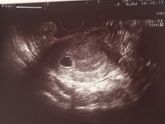

Девоньки,беременность 8 нед. Сегодня пошла вставать на учет, выписали дюфастон (как мне обьяснили,на всякий пожарный),то есть никаких анализов на гормоны предварительно я не сдавала,рез-ты узи хорошие,все соответствует сроку,никакой мазни и прочих нехороших … Читать далее